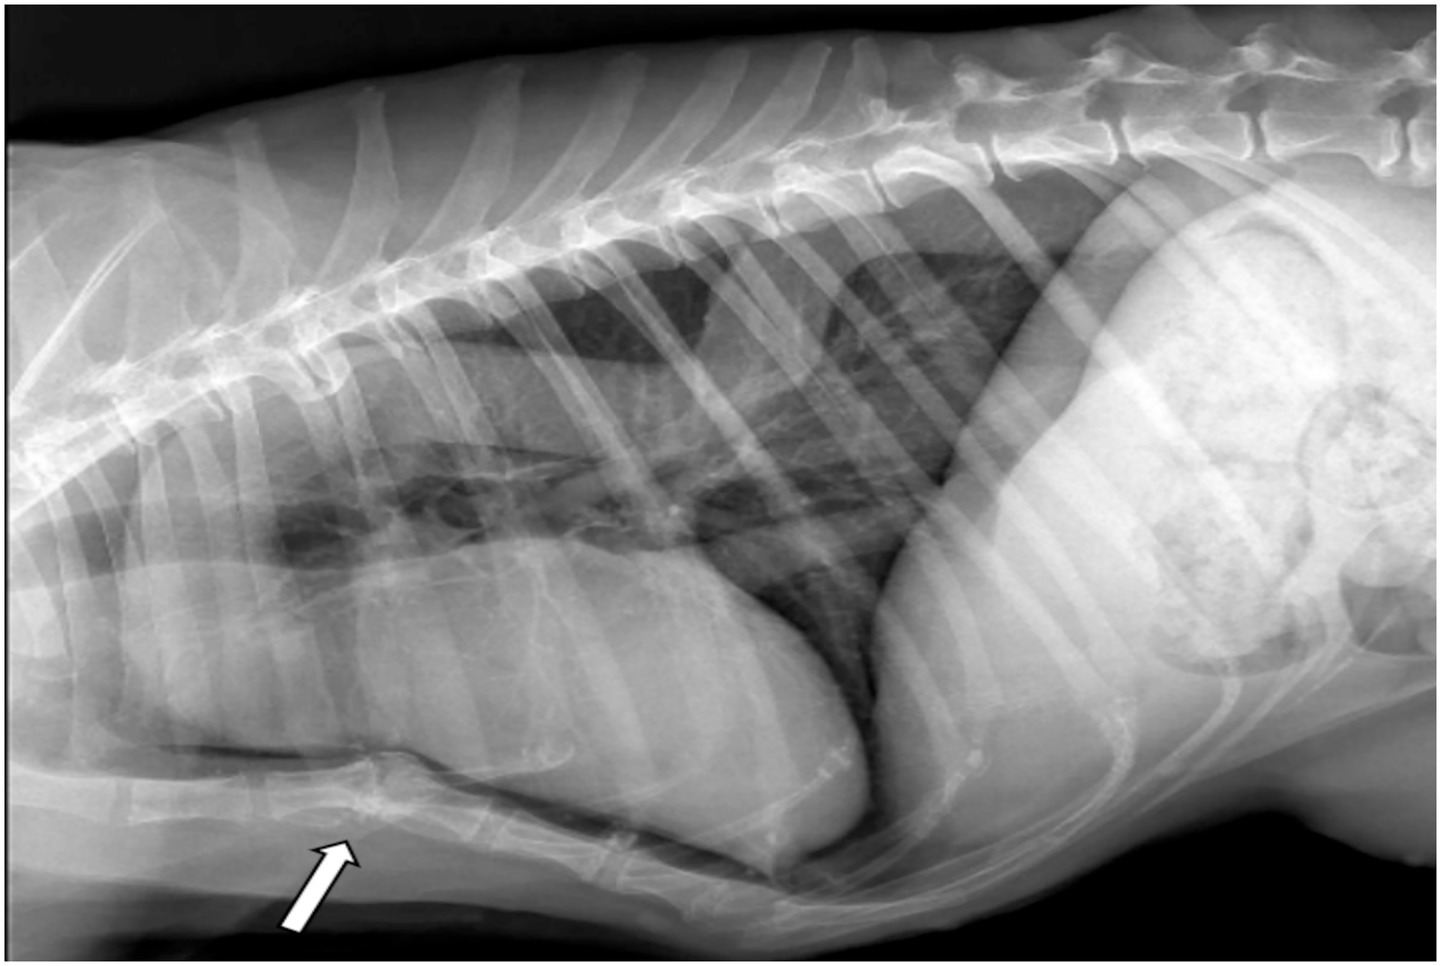

Right lateral thoracic radiography revealed an undulating thoracic aorta. Dilation was observed at the level of the aortic root and ascending aorta. However, the vertebral heart score (VHS) was 9 (reference range 8.5–10.6) (13). The patient had a left-sided scoliosis deformity at the lower thoracic and upper lumbar levels. In addition, sternum deformity revealed pectus excavatum (Figure 1). There was no history of trauma in the anamnesis.

Figure 1. Right lateral thoracic radiograph showing dilation of the proximal aspect of the aortic arch and the descending aorta extending toward the thoracic vertebrae. Note the ventrodorsal deviation of the sternum (arrow).

Another important differential diagnosis capable of producing similar pathological changes is MFS. The most common cardiovascular manifestation of MFS in humans is progressive dilation of the aortic root originating at the sinuses of Valsalva, followed by aneurysm formation and aortic dissection (18, 19). In this case, the greatest aortic enlargement was similarly located at the sinuses of Valsalva. Gradual, asymptomatic expansion of the aortic root can weaken the arterial wall and predispose it to acute ascending aortic dissection; however, no evidence of dissection was observed here. Additional systemic manifestations commonly reported in human MFS include excessive elongation of tubular bones, disproportionate limb length, chest wall deformities such as pectus excavatum or pectus carinatum, connective tissue laxity, joint hypermobility, and progressive scoliosis (12). In this dog, left-sided scoliosis at the mid-thoracic and cranial lumbar vertebrae was confirmed by CT, and pectus excavatum with additional spinal deformities was documented. Aortic undulation and dorsal deviation of the descending aorta may reflect elastic fiber fragmentation and medial degeneration, features frequently reported in MFS.